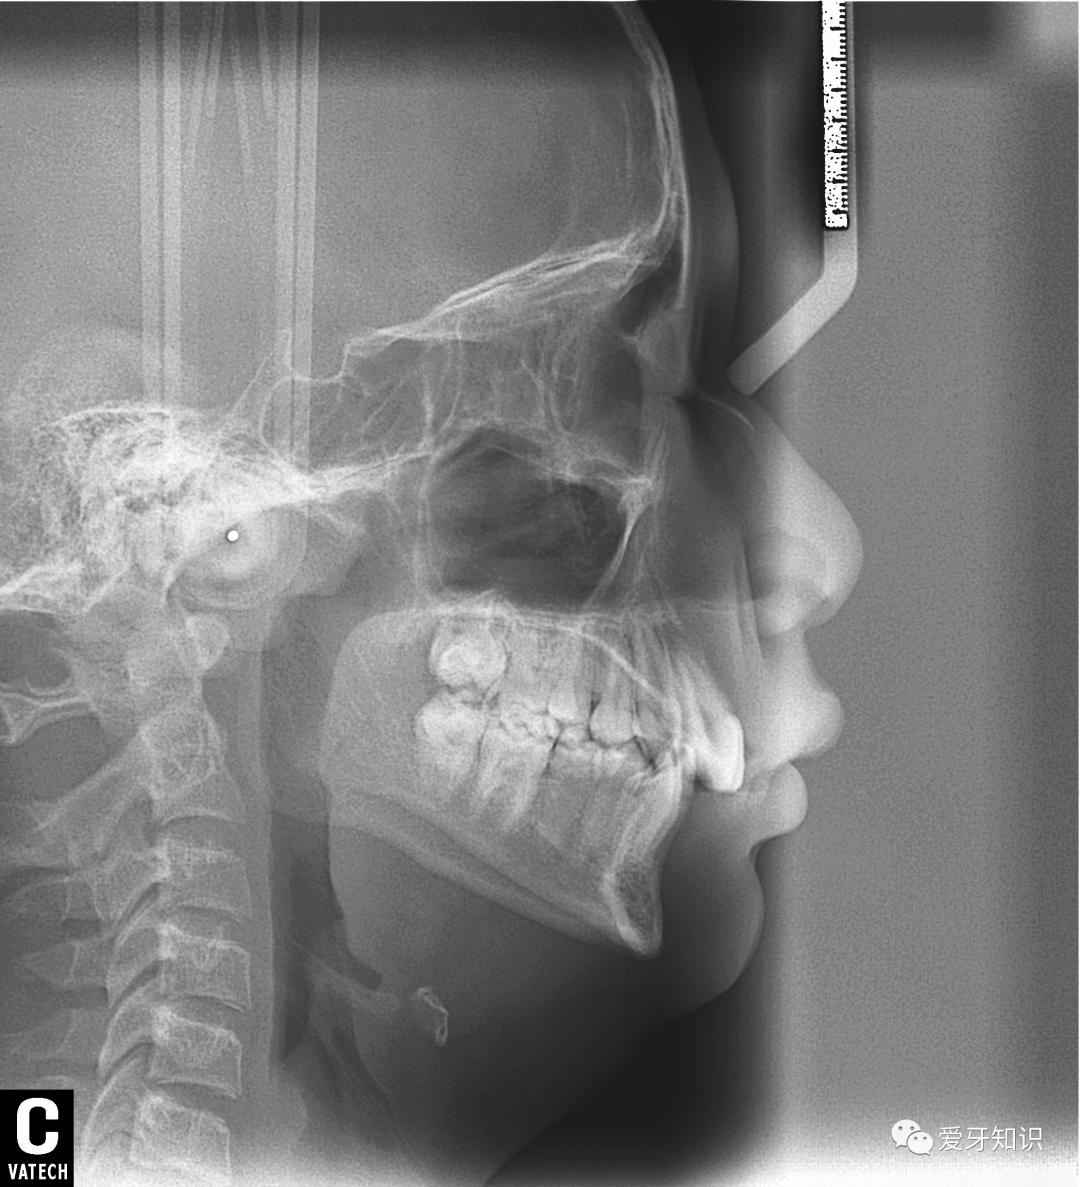

造成牙齿不整齐的原因具体能分为三种:牙性、骨性、功能性。说简单点就是牙有问题,骨头有问题,咬合有问题。网上有很多自行判断的方法,不过我还是建议拍片让医生来分析最靠谱。

拍了全景和侧位,就可以给你判断出来了。当然了,我的粉丝肯定是不收钱的了啊。免费拍全景片,侧位片,取模,设计矫正详细方案,都不要钱。只是给你多一个选择,多一份了解。